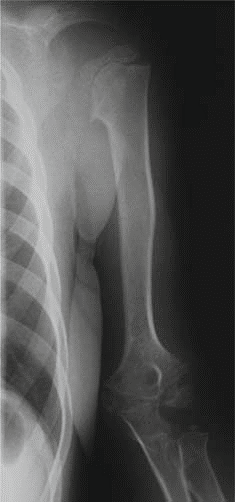

Additional Radiographs (Knees and Ankles):

To assess the widespread nature of MED, radiographs of other commonly affected joints were obtained.

* Knees: Revealed widened and irregular epiphyses of the distal femora and proximal tibiae. Patella alta was noted. Significant joint space narrowing was observed in the patellofemoral and medial tibiofemoral compartments. Mild valgus deformity was confirmed.

* Ankles: Demonstrated flattened and irregular talar domes, contributing to a widened ankle mortise and evidence of subtalar arthritis.

* This image typically represents an anteroposterior view of the knee, showcasing the irregular and flattened epiphyses, potentially widened and disorganized growth plates (if skeletally immature), and early degenerative joint changes consistent with the manifestations of Multiple Epiphyseal Dysplasia.